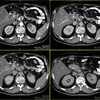

Почка – это парный орган, по форме напоминающий боб. В норме длина почки - около 11, ширина - 6 и толщина - 3 сантиметра, а вес – 120 – 200 г. В почке можно условно выделить плотную часть - паренхиму, состоящую из рабочих клеток и полую, состоящую из почечной лоханки и чашечек (см. рисунок). Часть рабочих клеток в паренхиме почки ответственна за выработку гормонов, витаминов и некоторых других веществ, другая же часть клеток образует особые структуры - нефроны, которые занимаются производством мочи. Вредные вещества и отходы продукты жизнедеятельности и азотистые шлаки удаляются из крови при помощи 2 млн. нефронов.